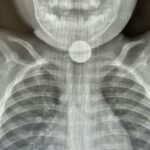

أحد متاجر SHEIN في كندا- صورة توضيحية- المصدر: ويكيميديا